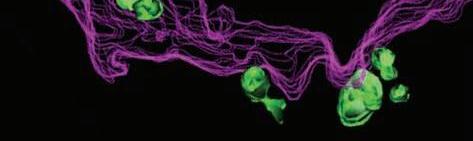

The intestine is home to a large collection of immune cells and bacteria. Epithelial cells in the intestine (green) separate the immune cells from bacteria.

Tumor cells in the intestine (green) express inflammatory factors (red).

A “CT scan” of a T cell being infected by HIV (courtesy of Benjamin K. Chen, MD, PhD)

Inflammatory cells (red) invade and destroy the thyroid gland in autoimmune thyroiditis.